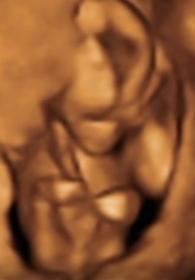

I'm supposed to be team green but since day 1 everyone has said they think it's a boy. I'm 27 weeks now and feeling anxious to find out! Here are some pics from the 16 week scan video. The pics I have from the 20 week scan don't show anything at all. Do you think thats a penis or could it be the cord or something?

Attachment 31150

Thanks Claire33 - I am starting to think it's a girl actually after watching the video a hundred times. Here is the 16 week video - it's mostly in 2d https://www.youtube.com/watch?v=LuYg...ature=youtu.be